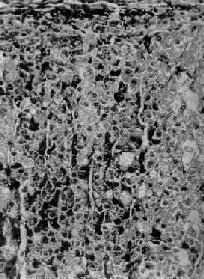

肾上腺皮质弥漫增生

图15-14 肾上腺皮质弥漫增生

图15-13之镜下观,肾上腺皮质束状带弥漫性增厚